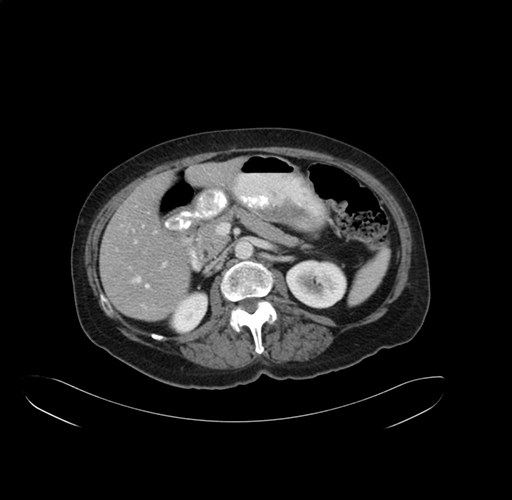

Pre-Chemo: Axial Venous

Axial Venous